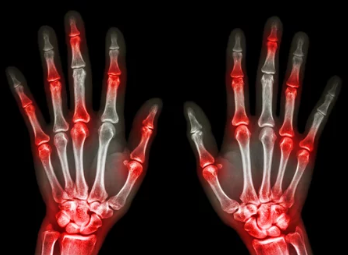

- 관절 부위의 발적, 부종, 열감: 엄지발가락 외에도 발목, 무릎, 손목, 팔꿈치 등 다른 관절 부위에도 통풍 발작이 발생할 수 있습니다. 관절 부위가 빨갛게 붓고 뜨거워지며, 심한 통증이 동반됩니다.

통풍 초기 증상이 의심된다면 류마티스내과 전문의를 찾아 정확한 진단과 치료를 받는 것이 중요합니다. 혈액 검사, 관절액 검사, X-ray 검사 등을 통해 통풍 여부를 확인하고, 약물 치료, 식이요법, 운동 요법 등을 통해 통증을 완화하고 재발을 방지할 수 있습니다.